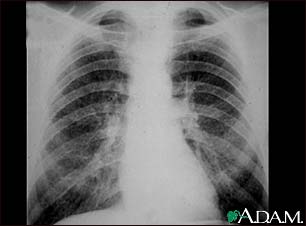

Coal workers pneumoconiosis - stage II

This chest x-ray shows stage II coal worker's pneumoconiosis (CWP). There are diffuse, small light areas on both sides of the lungs. Other diseases that may explain these x-ray findings include simple silicosis, disseminated tuberculosis, metastatic lung cancer, and other diffuse, infiltrative pulmonary diseases.